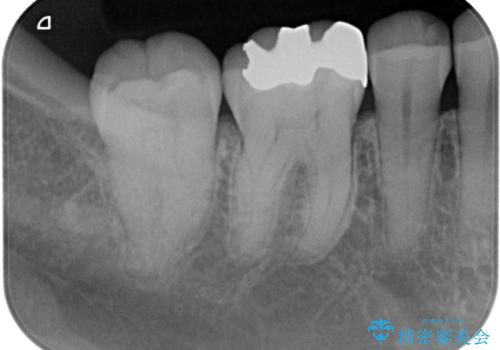

- 銀歯をやり替えたいとのことで来院された患者様です。金属の詰め物の大きさ、虫歯の範囲を考慮してオールセラミッククラウンでの治療をご提案しましたが、患者様のご希望であまり歯を削りたくないとのことでハイブリッドインレーでの治療を行うことにしました。

拡大鏡視野下で、金属の詰め物(メタルインレー)、虫歯の除去を行い、ハイブリッドインレーに適した形に整えました。